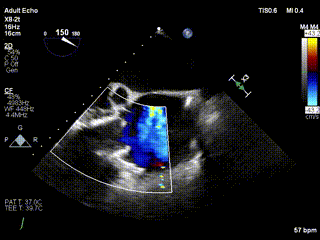

2021年12月24日,復(fù)旦大學(xué)附屬中山醫(yī)院葛均波院士團(tuán)隊(duì)成功應(yīng)用LuX-Valve Plus為一例極重度三尖瓣反流(TR)合并房顫、房缺的患者完成了經(jīng)血管三尖瓣置換術(shù),這是在前基礎(chǔ)上,本周完成的第三例經(jīng)血管三尖瓣置換手術(shù),葛均波院士、周達(dá)新教授等與心外科魏來教授、賴顥教授,心超室的潘翠珍教授、李偉教授及麻醉科的郭克芳教授共同完成了本周手術(shù),均獲得圓滿成功!患者術(shù)后超聲顯示無TR,臨床癥狀明顯改善。本周手術(shù)的成功也為L(zhǎng)uX-Valve Plus救治性臨床研究添上了濃墨重彩的一筆。

三例患者入院后,葛均波院士團(tuán)隊(duì)周達(dá)新教授、潘文志教授、張?jiān)床┦俊㈥惿┦考靶某业呐舜湔浣淌?、李偉教?/strong>對(duì)患者的情況進(jìn)行詳細(xì)評(píng)估和討論,最終決定為三例患者選擇LuX-Valve Plus40mm、50mm和50mm型號(hào)的瓣膜進(jìn)行手術(shù)治療。手術(shù)后即刻拔除氣管插管,術(shù)后患者三尖瓣反流癥狀得到顯著改善,復(fù)查心超結(jié)果顯示人工三尖瓣瓣膜支架固定穩(wěn)定,瓣葉關(guān)閉形態(tài)未見異常,未見明顯反流。